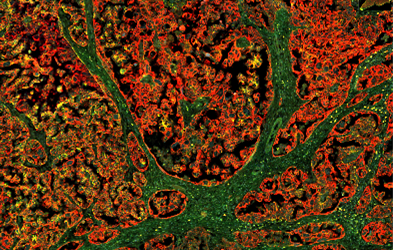

- Des modèles expérimentaux innovants (dont les modèles d’organoïdes tumoraux)

Nous développons des tests ex vivo sur des organoïdes dérivés de tumeurs de patientes, consistant à exposer ces modèles à différents traitements (médicaments, radiothérapie) afin d’évaluer leur efficacité à l’aide par exemple de tests biochimiques évaluant leur viabilité, de tests clonogéniques ou du test RECAP (évaluation de leurs capacités de réparation de l’ADN).

Ces travaux reposent sur des modèles expérimentaux de haute valeur :

- Organoïdes dérivés de tumeurs